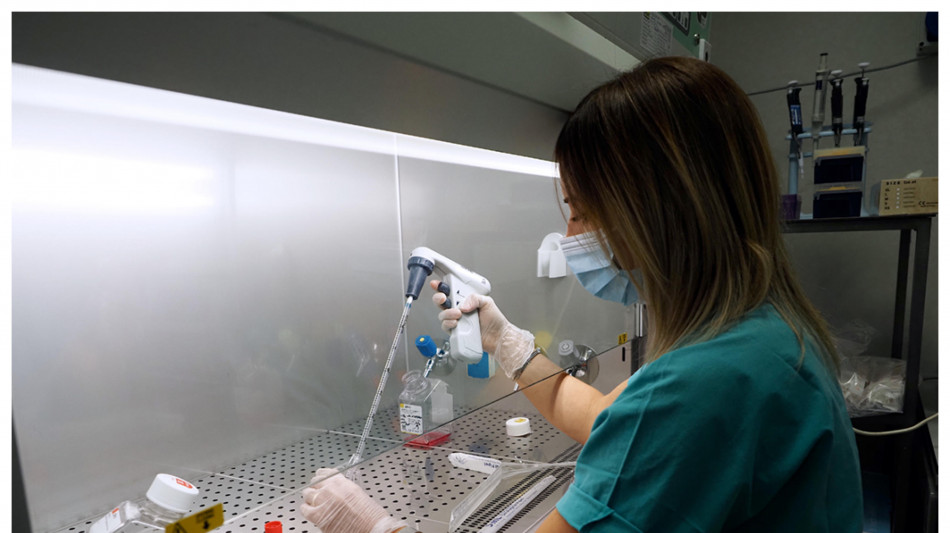

In una mappa i trucchi di uno dei superbatteri più comuni

Staphylococcus aureus, suggerisce nuove strade per combatterlo